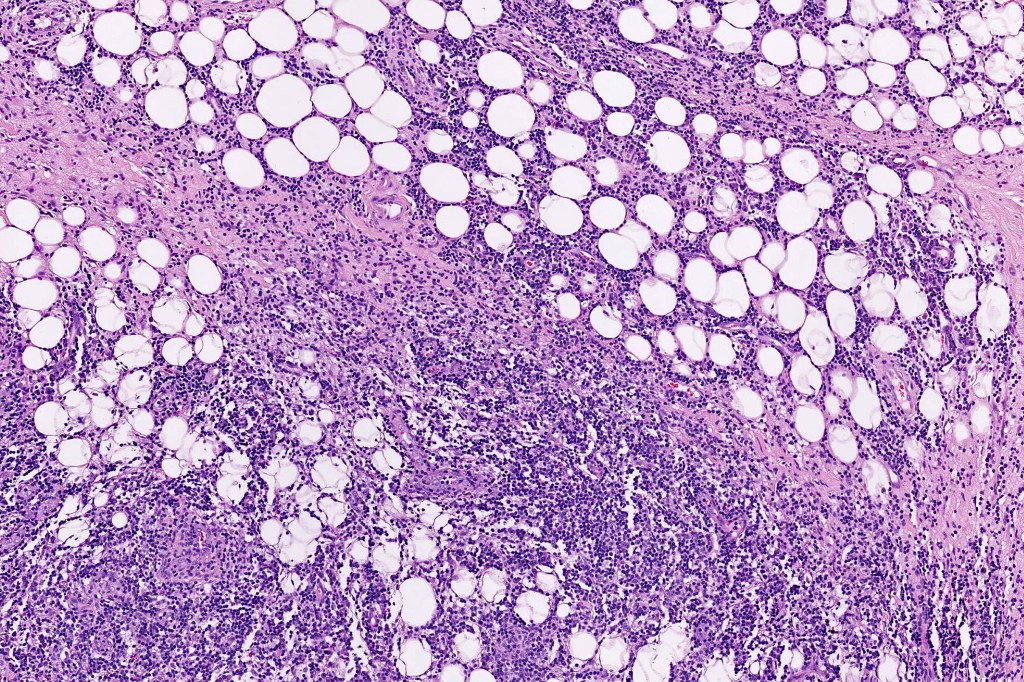

•Due to the admixture of pale histiocytes and lymphocytes, the scanning view is characteristic, and the diagnosis can be strongly suspected at this magnification

•Dense dermal nodular infiltrate sometimes extending into subcutaneous fat